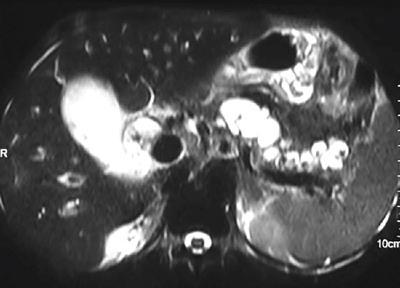

Shrinivas B. Desai, Ritu K. Kashikar, Shreya Shukla Radiological signs are classical and distinctive abnormalities characteristic of a disease. These can be seen on any imaging modality. Resemblance to commonly seen objects and patterns form the basis of radiological signs. The aim is to help the reader associate, understand and memorize these pathologies with the aid of signs. Various signs pertinent to hepatobiliary system are described in the chapter. Described on MRI when liver lesion shows a peripheral rim of high T2 signal intensity with the centre of the lesion appearing isointense to the background of noncirrhotic liver on T2WI mimicking an atoll. It is considered a characteristic sign of an inflammatory hepatic adenoma (image) but is only seen in about one-third of cases Extrinsic smooth impression over medial aspect of duodenum along its posteroinferior aspect, seen in pancreatic head pathologies like carcinoma. This sign is seen in pancreatic adenocarcinoma Presence of a persistently hyperattenuating dot within a lesion on arterial and portal venous CT. This corresponds with peripheral nodular enhancement seen on dynamic MR. Presence of bright dot suggests that the lesion is a hemangioma and helps in ruling out metastasis Ultrasound appearance of multiple cystic spaces or lesions that has been used to describe the appearance of an intraductal papillary mucinous neoplasm of the pancreas. Seen on contrast CT in portal hypertension. The appearance is based on resemblance to Medusa from Greek mythology. Dilated engorged paraumbilical veins radiating across umbilicus to join systemic veins is seen. This sign is seen in Caroli’s disease on contrast CT. Enhancing dots within dilated intrahepatic bile ducts represent portal radicles. Caroli’s disease Irregularly dilated pancreatic duct with multiple strictures and intervening dilatation with associated dilated side ductules resemble multiple lakes supplied by a single territory. Best seen in MRCP images. Chronic pancreatitis It is a finding on MRI and CT and is best seen on MRI T2-weighted and postcontrast T1-weighted sequences. Small necrotic/purulent areas in the pyogenic abscess ‘cluster’ together and then coalesce into a larger necrotic/purulent areas, eventually becoming a larger septated abscess cavity. At the periphery of these clusters: Associated with pyogenic hepatic abscesses and can help differentiate pyogenic abscesses from other types of liver lesions Abrupt termination of gas within the proximal colon at the level of radiological splenic flexure. The inflammatory exudates in pancreatitis extend to the phrenicocolic ligament giving rise to this sign Seen on grey scale ultrasound as a reverberation artifact when small calcific or highly reflective objects are imaged. The colour comet-tail artifact is an ultrasonographic sign seen in a number of situations when colour Doppler scanning is performed. This sign occurs in cases of traumatic right-sided diaphragmatic rupture with resultant partial herniation of liver through the defect. Separation of the herniated liver from its intra-abdominal component is via a small constriction at the level of diaphragm resembling a cottage loaf. Cottage loaf is a particular shape of bread in which larger and smaller roughly spherical balls are squashed together. Traumatic right-sided diaphragmatic rupture with resultant partial herniation of liver Bile eccentrically outlines luminal stone, creating a low attenuation crescent. Best seen on MRCP images. Choledocholithiasis Dilatation of both pancreatic duct and CBD is referred to as the double duct sign. Positive double duct sign suggests the diagnosis of carcinoma of the head of the pancreas and ampullary tumours and is hence considered ominous. Occasionally the sign may be seen in impacted gallstone in the distal duct. This feature is seen in patients with liver abscess on contrast-enhanced CT. A double, inner hyperattenuating and outer hypoattenuating rim is seen surrounding the hypodense abscess. The inner hyperattenuating rim corresponds to the enhancing abscess membrane, while the outer rim corresponds to the edema of the surrounding liver which appears hypodense and may show delayed enhancement. Liver abscess A positive duct penetrating sign is when a mass is penetrated by an unobstructed pancreatic duct; this makes focal pancreatitis the most likely cause rather than pancreatic carcinoma. This sign is best appreciated on MRCP (or ERCP). A radiographic sign that can be useful in differentiating between focal pancreatitis (inflammatory pancreatic mass) from pancreatic carcinoma. The duct-penetrating sign on MRCP is more helpful in differentiating between these two entities than a delayed enhancement pattern on CT or MRI It occurs when there is both limy bile and a gallstone in the common bile duct. The linear vertical radiopaque bile forms the line of the exclamation mark (i.e. !), whilst a more distal calculus forms the ‘dot’ at the end of the exclamation mark. Pathognomonic imaging sign of the rare diagnosis of limy bile on plain abdominal radiography Nonenhancing ruptured lesion with peripheral rim enhancement showing discontinuity from the rest of the liver and protruding from the liver surface is called the enucleation sign. Ruptured HCC Enlargement of the pericholecystic space. One of the signs of liver cirrhosis Can be seen on technetium 99m sulphur colloid scans of the liver and spleen, as well as CT studies. It occurs as a focal area of increased radiopharmaceutical uptake in the medial segment of the left hepatic lobe (segment IV) occurring as a result of SVC obstruction and portosystemic venous shunting between the superior vena cava and the left portal vein via the internal thoracic and paraumbilical veins. The equivalent of this sign may also be seen on contrast-enhanced CT scans as a hypervascular region. Budd–Chiari syndrome causes the hot spot sign in the caudate lobe